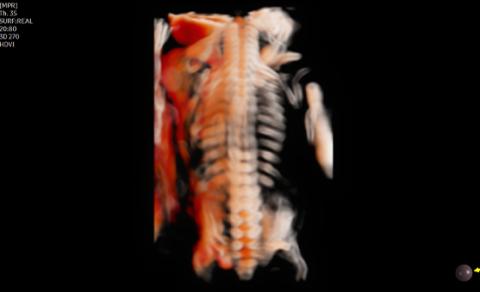

CrystalLive™ in 3D/4D provides users with more realistic and high-resolution images. It outdoes conventional 3D imaging technologies in terms of viewing small parts and lighting effects. In addition, you are able to see 3D anatomy with more realistic depth perception, and can visualize the internal and external structures at once.

CrystalVue™ is an advanced volume rendering technology that enhances visualization of both internal and external structures in a single rendered image using a combination of intensity, gradient and position.

RealisticVue™ ¹ displays high resolution 3D anatomy with exceptional detail and realistic depth perception. User selectable light source direction creates intricately graduated shadows for better defined anatomical structures.